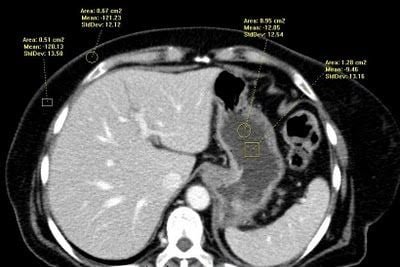

Densitometría (medición de densidad)

Cuando no exista la certeza de la naturaleza de un fluido, la medida de la densidad del líquido permitirá aclarar el diagnóstico diferencial. Sin embargo, no es aconsejable efectuar mediciones de voxels únicos pues esos datos están sujetos a fluctuaciones estadísticas que pueden hacer poco fiable su atenuación. Proporciona mayor exactitud colocar una más amplia «región de interés» (ROI) que contenga varios voxels, sobre una lesión focal, una estructura, o una colección líquida. El ordenador calcula los niveles de densidad media de todos los voxels, obteniendo también la desviación estándar.